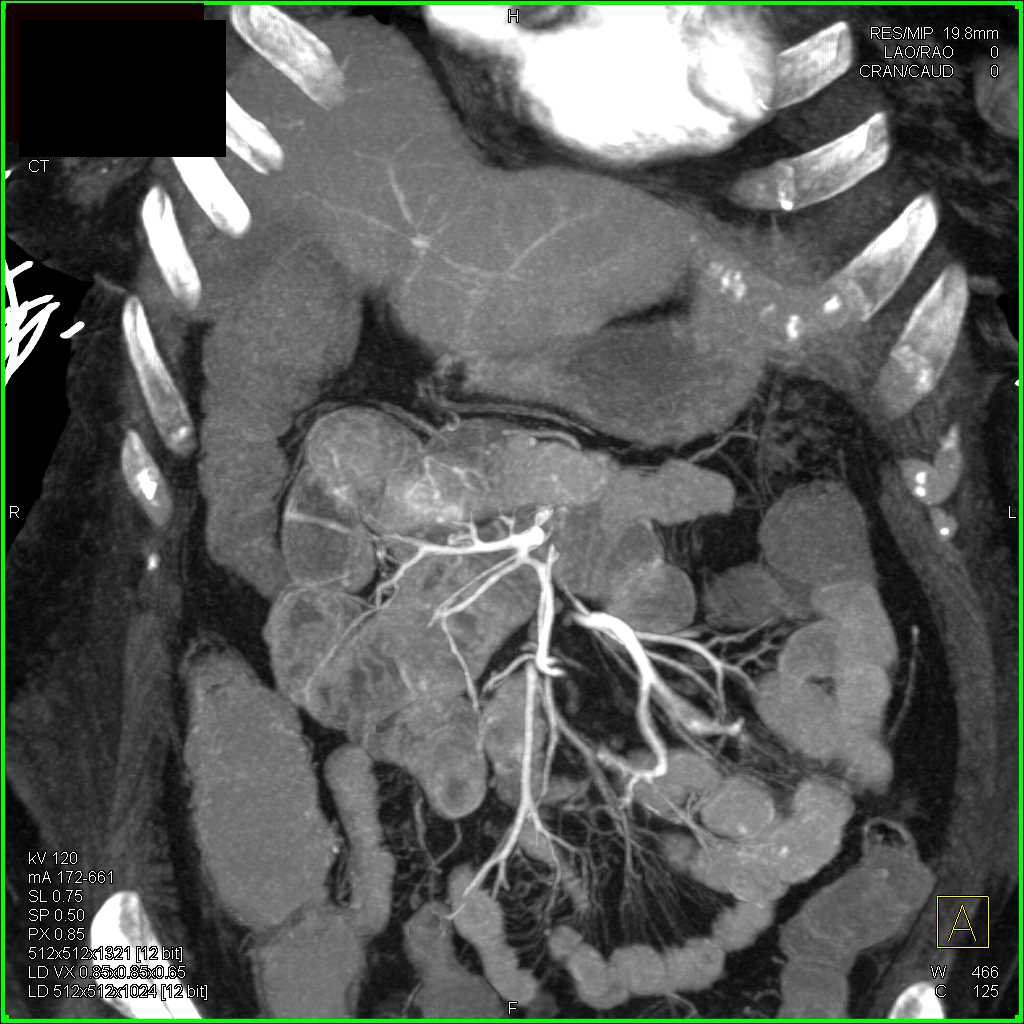

Carcinoid Tumor in the Root of the Mesentery